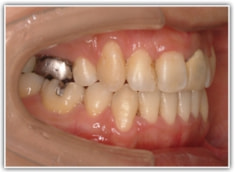

治療後(2年3ヶ月後)

歯根のパラレリング(平行性)が獲得されております。

下顎8番は、両側抜歯済みです。